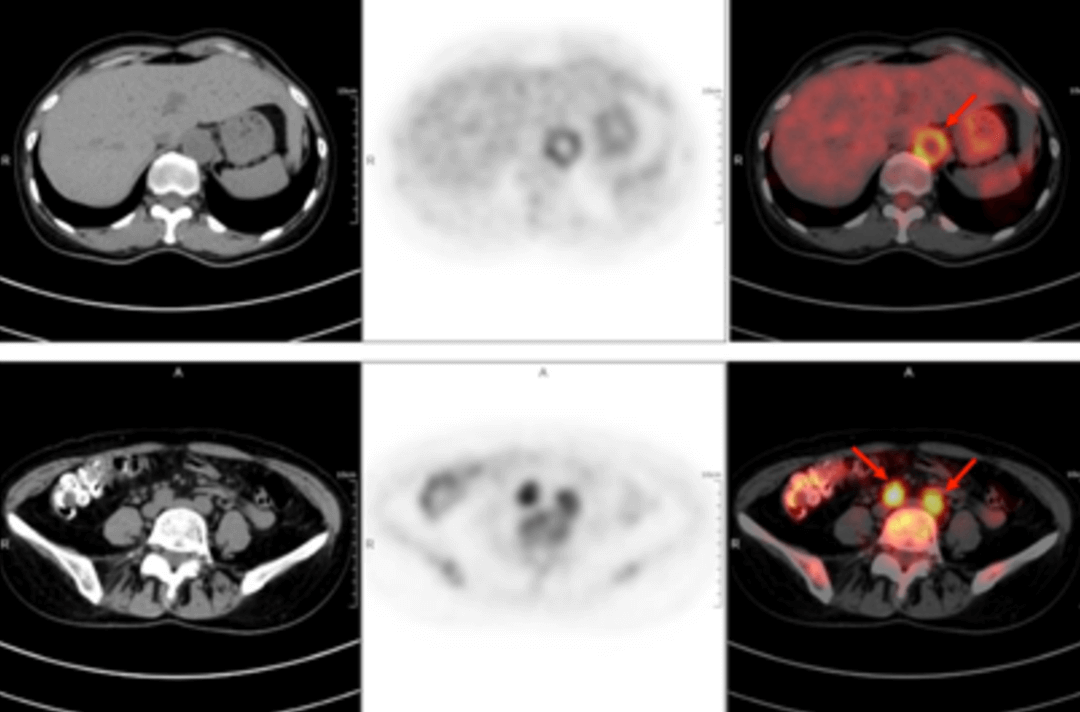

A 58-year-old women went to the hospital for intermittent fever for more than 40 days. Her highest body temperature was 38.9℃. Other symptoms included fatigue and shoulder joint pain which were especially acute in the afternoon and at night without cold, chills, sputum, hemoptysis, chest pain, chest tightness and shortness of breath. After two weeks of intravenous administration of "cephalosporin antibiotics" there was no improvement, and intermittent fever continued. The outpatient clinics noted the patient had "fever of unknown origin." There were no obvious diagnostic features upon physical examination. The results of a routine blood test were as follows: erythrocyte sedimentation rate in the first hour: 72mm; high-sensitivity C-reactive protein: 204. 20mg/l. Then, the patient had a whole-body F-FDG PET-CT examination to find the cause of the fever of unknown origin.

In the PET/CT images, wall thickening with increased glucose metabolism occurred in several parts of the body (bilateral internal carotid artery, common carotid artery, brachiocephalic trunk, bilateral subclavian and axillary arteries, thoracic aorta, abdominal aorta, bilateral common iliac artery, internal iliac artery, external iliac artery and femoral artery), which was considered to be caused by inflammatory changes. Combined with the patient's medical history, clinical symptoms, examination and imaging findings, she was diagnosed with T.A. After standardized anti-inflammation treatment, her body temperature dropped and her condition improved.